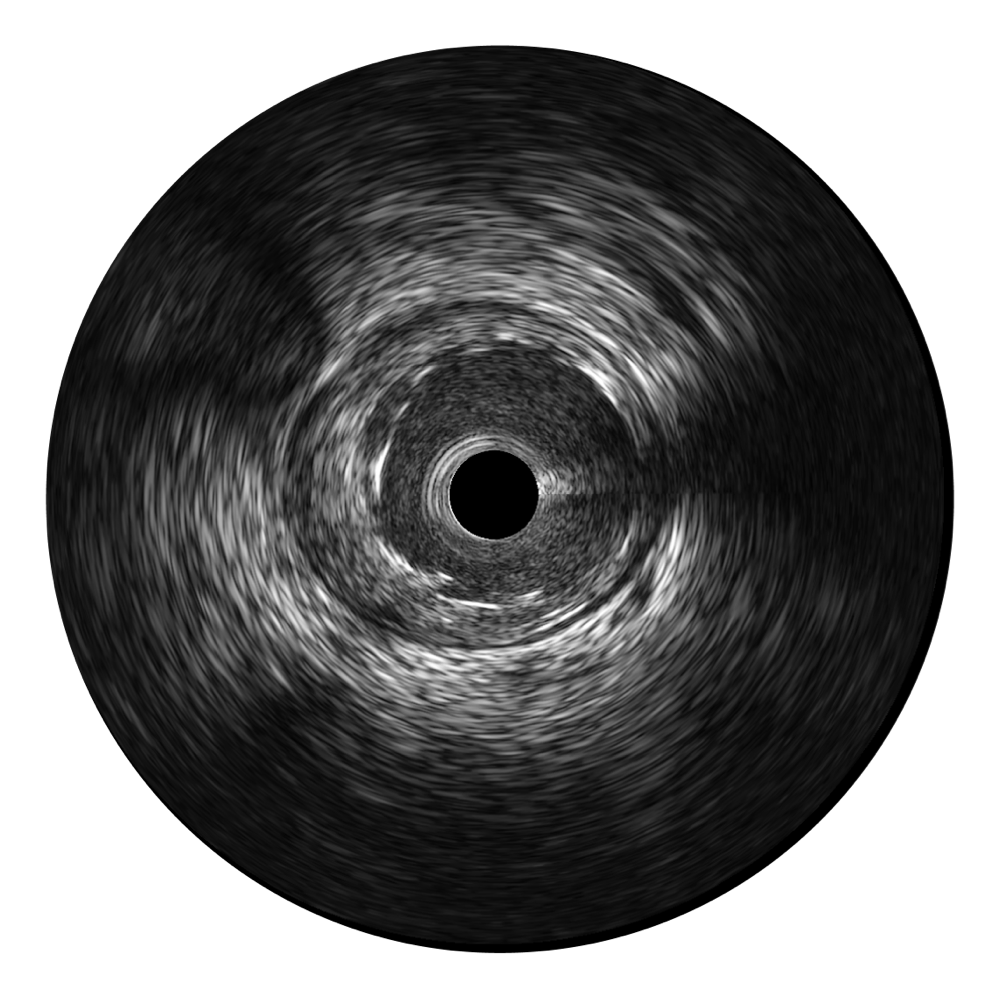

临床图

远场分支血管及导丝

支架内血栓

组织脱垂